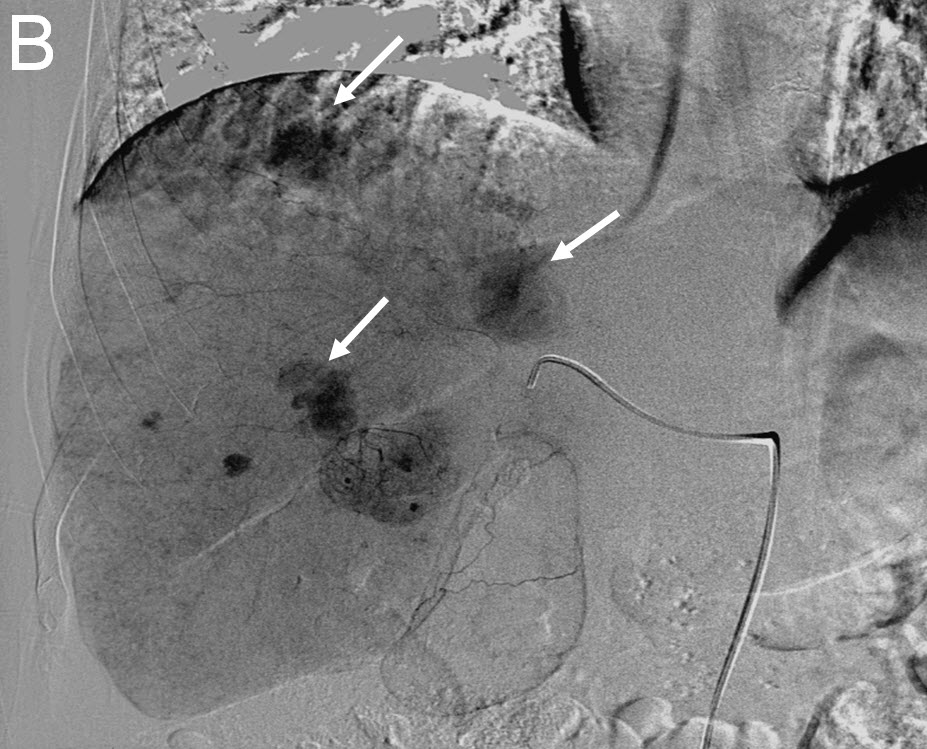

Treating Multiple Liver Tumors with Drug Eluting Beads (DEB TACE)

| (B) Delayed right liver angiogram showing multiple tumor "blushes" |